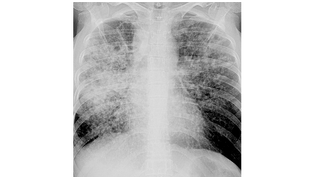

10:151,0×00:00/10:15Клиника туберкулеза онлайн234 смотрели · 10 месяцев назадПодписатьсяДиссеминированный туберкулез